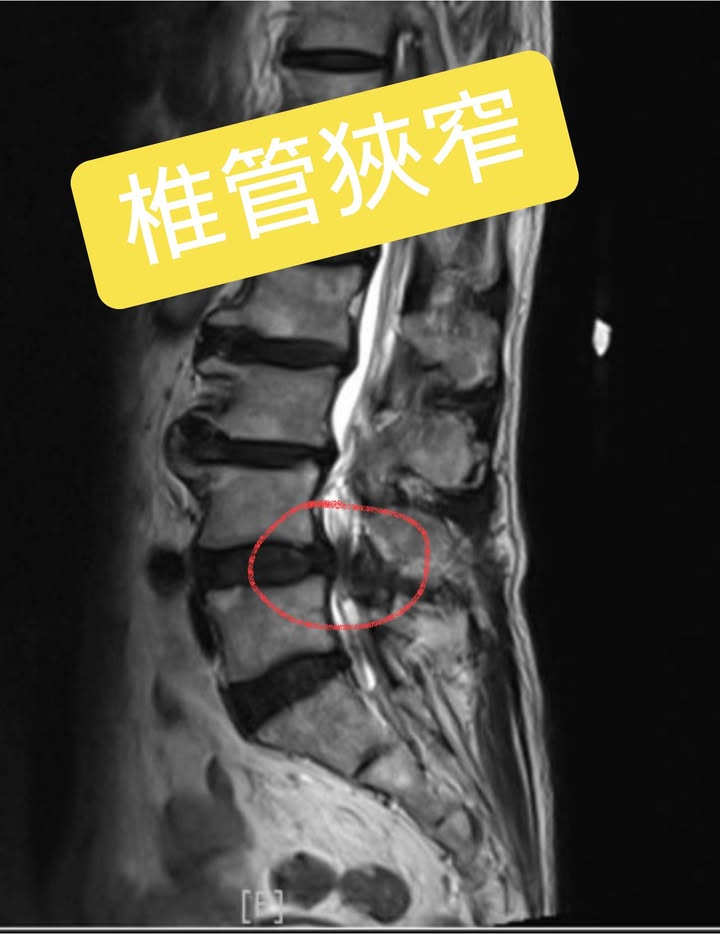

Cervical Spine Treatment Cases 腰椎治療案例 #腰椎滑脫合併椎管嚴重狹窄醫案 #感謝台中市北屯區呂阿姨熱情見證 #原本腰腿疼痛到快... 2022.01.04 #八十老翁腰椎手術兩次仍然不理想 #治療前無法在忠孝東路走超過一分鐘 #忠孝復興交會... 2021.12.29 感謝台看過四家復健科、骨科、醫學中心、整骨,依然效果不如預期,右腳依然麻痛到不行... 2022.02.18 #腰椎滑脫合併嚴重椎管狹窄醫案 #兩個醫學中心骨科醫師都建議開刀 #感謝基隆市信義區... 2021.12.22 ⭕️下背手術失敗綜合症候群 🔲腰椎做過一手術切除骨刺 ‼️半年後又開始復發了 ✳️晨起疼... 2022.01.29 🔎腰椎滑脫心酸血淚史 ‼️原本右腳無法走路合併膝蓋痠軟無力 ✅治療六週徹底改善所有症... 2021.12.14 #腰椎間盤巨大突出脫垂 #原本預計下周要開刀了 #最後真的逆轉勝 #來診前已經痛到無法... 2022.01.29 ‼️巨大椎間盤突出脫垂大痛到無法走進診間 ★醫學中心神外醫師認為可能要開刀 ㊣脊椎整... 2022.01.20 #嚴重的頸椎壓迫導致下肢走路無力 #頸椎整合中醫微創療法逆勝 #頸椎壓迫還會導致腳部... 2021.12.04 ⭕️嚴重椎管狹窄治療醫案 ⁉️將近快半年的疼痛到後來已經快無法走路 ❌走路嚴重跛行何必... 2021.12.09 #天才年輕賽車手巨大椎間盤突出 #之前八周治療完全逆轉勝康復 #提供治療前後核磁共振... 2021.12.02 #上位腰椎L2L3椎管嚴重狹窄案例 #之前痛到無法工作上班快兩個多月 #卡通圖一張秒懂何... 2021.12.01 #腰椎管狹窄一定要急著做手術嗎 #當初痛到走路無法超過二十分鐘 #兒子上網遍尋醫師... 2021.11.26 ⭕️下背手術失敗綜合症候群 🔲腰椎做過三次手術打了五組鋼釘子 ‼️右腳疼痛到連坐輪椅都... 2021.11.25 #感謝台北市文山區蔡先生熱情見證 #右腳痠麻脹痛到嚴重影響日常生活 #腰椎整合微創筋... 2021.11.18 ← 上一頁 5 6 7 8 9 下一頁 →